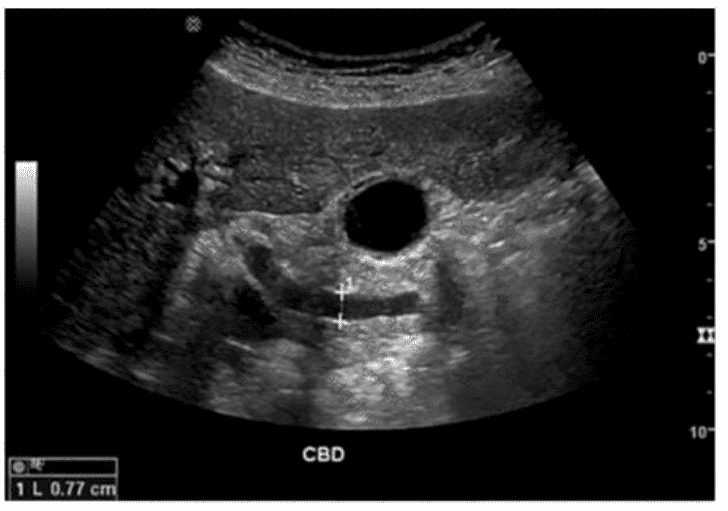

QUESTION DESCRIPTION:

Which condition is most likely associated with this image of the common bile duct?

Correct Answer & Rationale:

Answer: C

Explanation:

The ultrasound image demonstrates a dilated common bile duct (CBD), measuring approximately 7.7 mm in diameter. A normal CBD should generally measure less than 6 mm in a patient under 60 years old and may increase approximately 1 mm per decade thereafter or after cholecystectomy.

In the absence of gallstones within the CBD, one of the most concerning causes of CBD dilation is distal obstruction due to an extrinsic compressive lesion. The most common and clinically significant cause of distal CBD obstruction is a mass at the head of the pancreas.

A pancreatic head mass (e.g., adenocarcinoma) may compress the distal CBD and pancreatic duct simultaneously, resulting in the “double duct sign” — dilation of both the CBD and pancreatic duct. This is a classic finding in pancreatic cancer.

Comparison of answer choices:

A. Liver mass — unlikely to cause isolated CBD dilation unless invading the porta hepatis.

B. Cystic duct stone — may cause gallbladder hydrops but typically not CBD dilation unless Mirizzi syndrome is present.

C. Pancreatic head mass — Correct. This is the most likely cause of painless progressive CBD dilation without visible intraductal stones.

D. Gallbladder stones — These may be associated with biliary colic or cholecystitis but typically do not cause CBD dilation unless the stone has migrated and obstructed the distal duct.